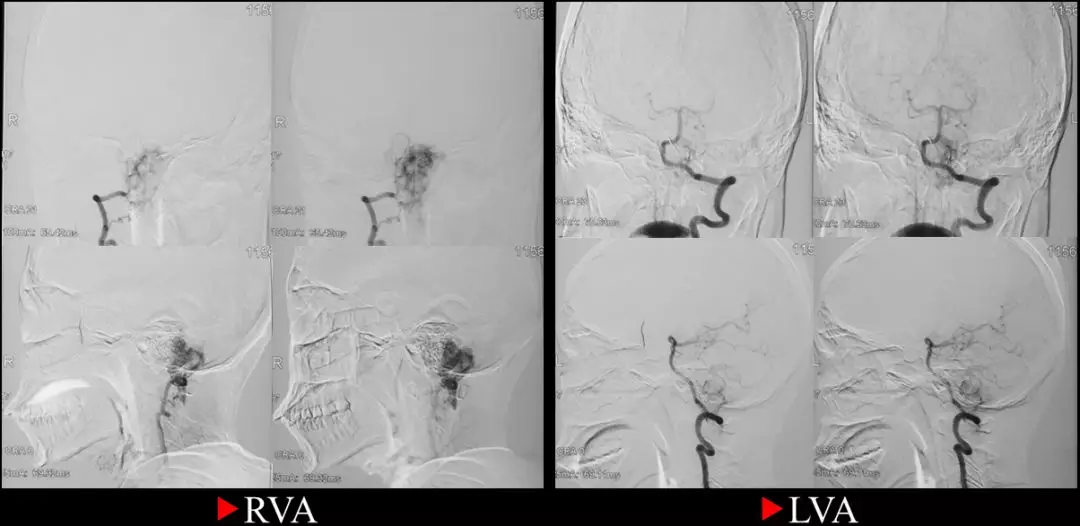

2017-7-26:患者平卧于DSA复合手术床上,全麻成功后,双侧腹股沟常规消毒铺巾,以Seldinger技术穿刺右股动脉,置入5F导管鞘,导丝支撑下,将5F导引导管超选入右侧椎动脉内,复查造影证实颅颈交界处肿瘤明显异常染色,主要由右侧椎动脉肌支和脑膜后动脉供血,旋转后选择工作角度,在Traxcess 0.014微导丝支撑下将Echelon-10微导管超选入右侧椎动脉肌支,手推造影证实远端无正常血管后以5%葡萄糖溶液冲洗管腔,然后路径图下用15%Glubran胶缓慢栓塞此处血供,注入约0.4ml栓塞剂后出现返流,停止注射,撤出微导管。

然后用同样方法将另一根Echelon-10微导管超选入脑膜后动脉,同法注射Glubran栓塞剂约1ml,见栓塞剂在肿瘤内部弥散理想,复查造影见左侧椎动脉肿瘤血供完全栓塞,撤出微导管,再将导引导管超选入左侧椎动脉,复查造影发现肿瘤尚有少量来自左椎动脉的血供,但无合适栓塞动脉,肿瘤血供总体栓塞约80%,留鞘行开颅肿瘤切除术。

术中DSA

术中栓塞前后结果比较